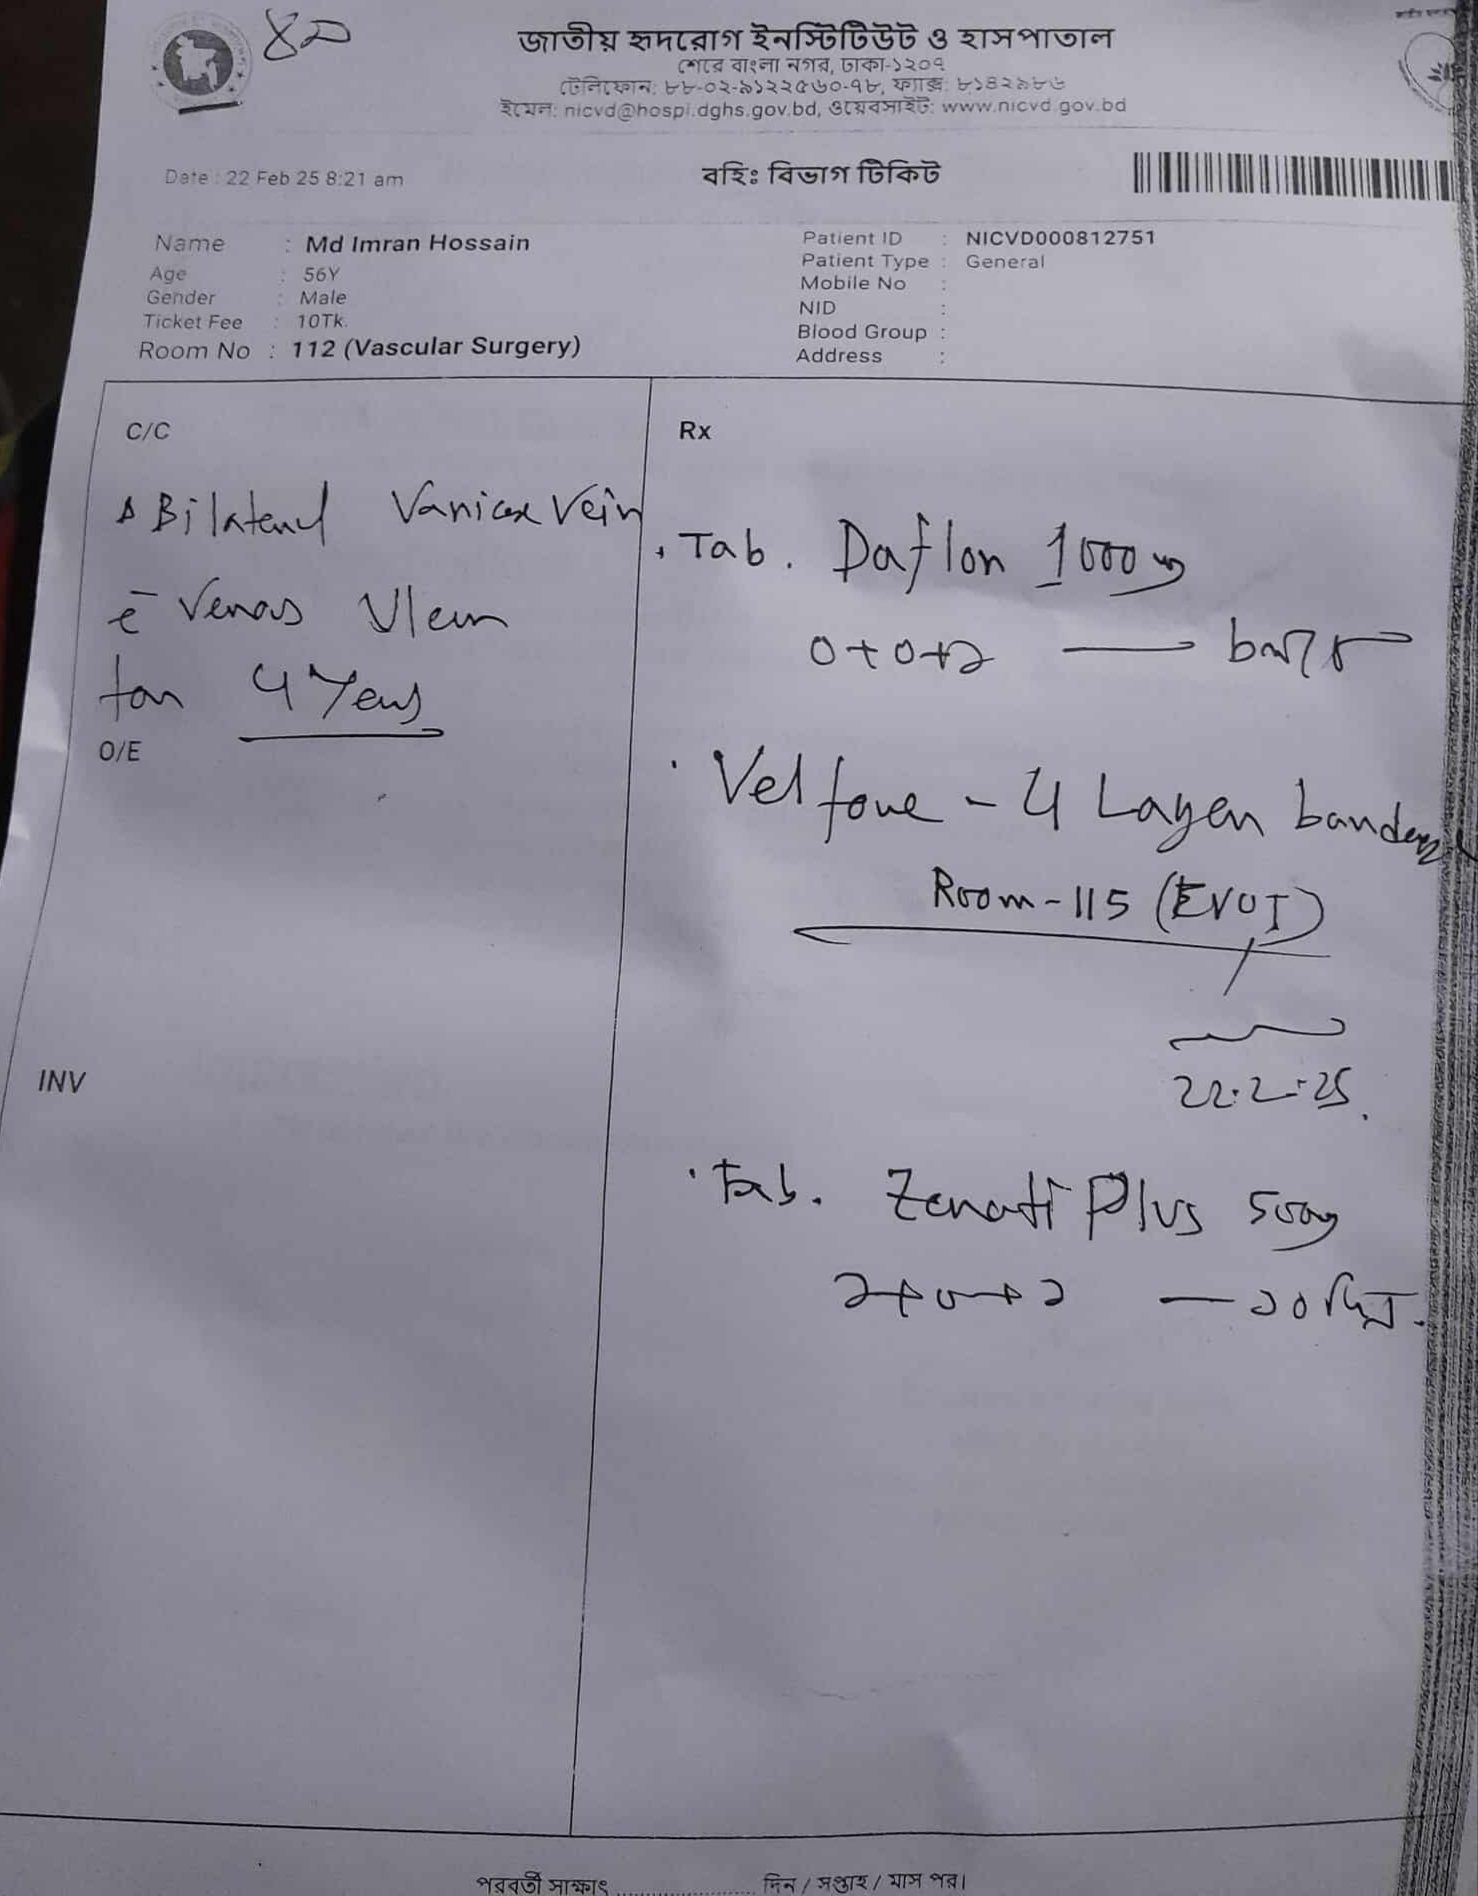

#250927D: ভয়াবহ পায়ের ক্যান্সারে আক্রান্ত মোঃ ইমরান হোসেন অপারেশনের জন্য সাহায্যের আবেদন, গ্রাম: চকলোকমান কলোনি, জেলা : বগুড়া।